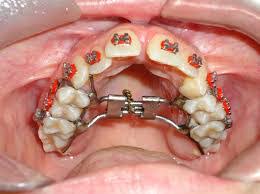

Disjuntor mais utilizado em disjunções rápidas da maxila. O HYRAX é um aparelho expansor preso aos dentes pela parte interna junto ao céu da boca. Quanto ao hyrax espero também não ter que ativa-lo mais.

Ortodontia E Arte Posso Usar Hyrax E Aparelho Fixo Ao Mesmo Tempo

Ele é usado em casos que o osso maxilar é muito estreito.